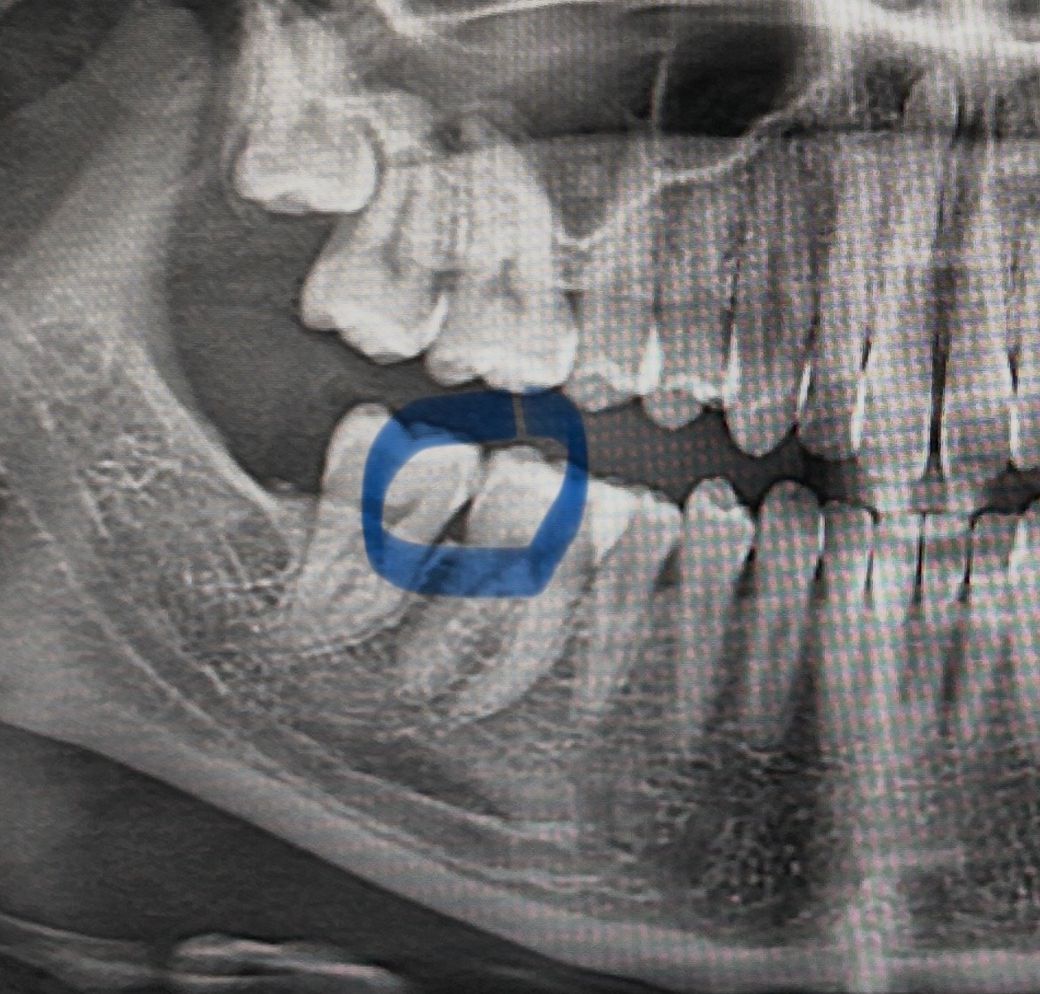

오늘 검사랑 스케일링 받으려고 치과를 다녀왔는데,

이 부분 충치일까요? 의사선생님께서는 치실 열심히 하고 1년에 한 번씩 스케일링 받으러 오라는 말씀만 하셔서요... 괜히 걱정 되네요 ㅠㅠ

치아끼리 중첩되어 엑스레이상 저렇게 보이는 경우가 많습니다 가장 확실한 건 작은 엑스레이사진을 찍어보는겁니다